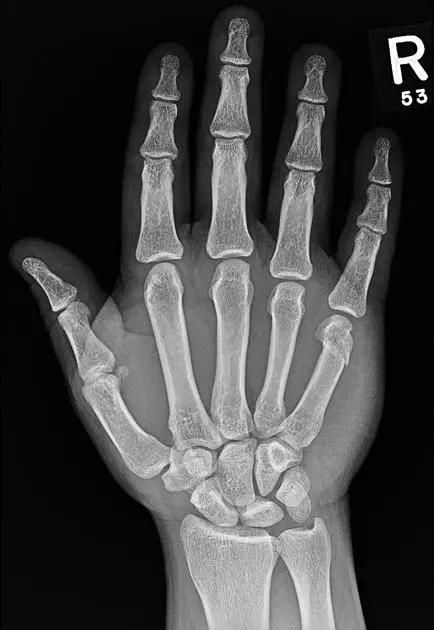

手腕部骨折

7. Boxer's 骨折

第 5 掌骨颈骨折伴有掌骨头向掌侧移位。

(来源:Radiopaedia)